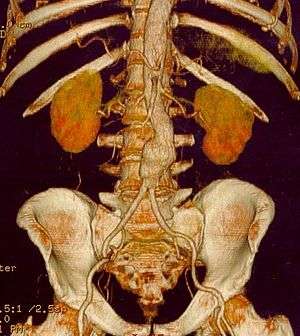

|

CT reconstruction image of an abdominal aortic aneurysm | |

The diagnosis of an abdominal aortic aneurysm can be confirmed at the bedside by the use of ultrasound. Rupture may be indicated by the presence of free fluid in the abdomen. A contrast-enhanced abdominal CT scan is the best test to diagnose an AAA and guide treatment options.

A rapidly expanding aneurysm should under normal circumstances be operated on as soon as feasible, as it has a greater chance of rupture. Slowly expanding aortic aneurysms may be followed by routine diagnostic testing (i.e.: CT scan or ultrasound imaging).